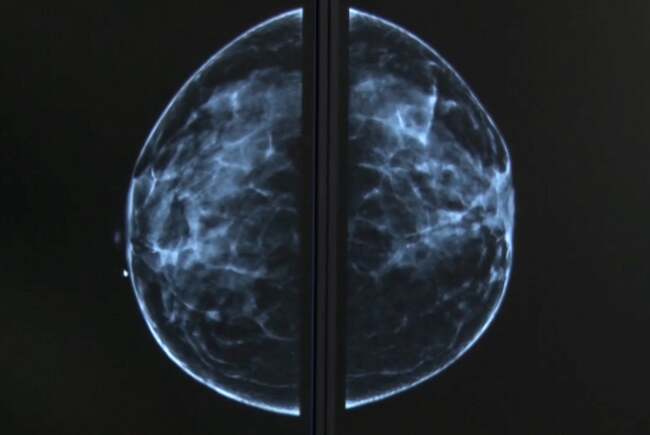

Spitalul „Victor Babeș” Timișoara se alătură campaniei de realizare gratuită a mamografiilor de sân, alături de Spitalul Municipal Timișoara. Acestea sunt oferite femeilor din vestul țării, cu vârsta între 50 și 69 de ani. Peste jumătate dintre pacientele investigate trebuie să provină din mediul rural.

Spitalul „Victor Babeș” din Timișoara și-a anunțat implicarea într-o campanie importantă de realizare gratuită a mamografiilor de sân, alături de Spitalul Municipal din același oraș. Această inițiativă este destinată exclusiv femeilor din vestul țării, cu vârsta cuprinsă între 50 și 69 de ani. În plus, peste jumătate dintre pacientele investigate trebuie să provină din mediul rural.

În contextul actual, în care incidența bolilor oncologice este în creștere, este esențial ca femeile să acorde o atenție deosebită sănătății lor mamare. Mamografiile de sân reprezintă una dintre cele mai eficiente metode de depistare precoce a cancerului de sân, oferind șanse mari de vindecare în stadiile incipiente ale bolii.

Prin intermediul acestei campanii, Spitalul „Victor Babeș” din Timișoara își propune să ofere acces gratuit la mamografii pentru femeile din vestul țării, în special pentru cele cu vârsta cuprinsă între 50 și 69 de ani. Această grupă de vârstă este considerată una dintre cele mai susceptibile la dezvoltarea cancerului de sân, motiv pentru care screeningul periodic este deosebit de important.